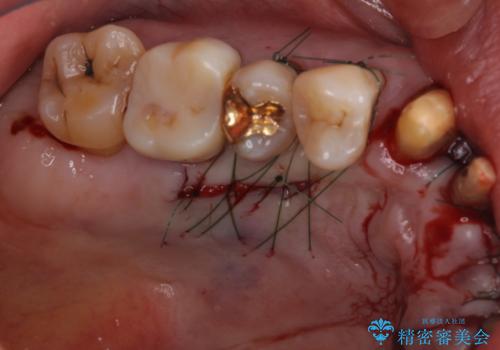

上顎の奥歯は全体的に歯周ポケットが散見され出血が認められたため、歯周外科処置を行うこととしました。

上の歯は見た目を良くしたいというご希望があったため、歯周外科処置を行った歯についてはセラミッククラウンで補綴することとしました。

- 外科手術のため、術後に痛みや腫れ、違和感を伴います

- 歯周組織再生治療は患者様の状態によって術後の経過が異なります(見た目が改善しない場合もあります)

- 歯周組織再生治療は自費診療(保険適用外)となります